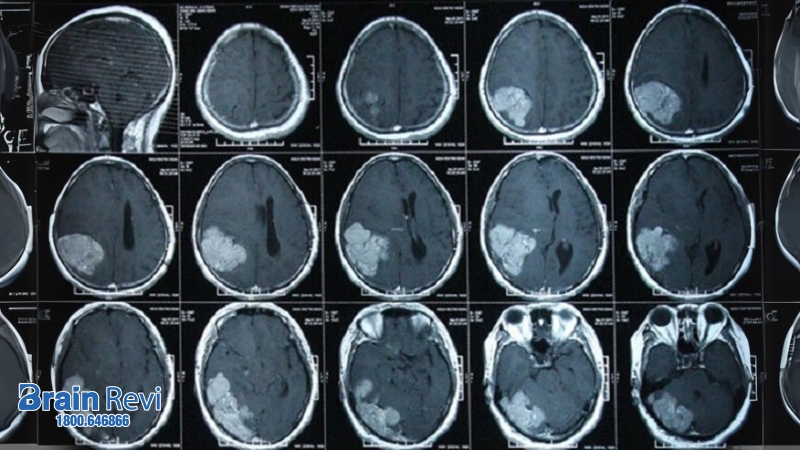

Chỉ định xét nghiệm hoặc chụp CT và MRI

Sau đó, tuỳ thuộc vào tình trạng bệnh của bác sĩ có thể cân nhắc và chỉ định kiểm tra vùng đầu và não thông qua các biện pháp chẩn đoán hình ảnh như chụp X- quang đầu, chụp CT, chụp MRI,… Trong đó, biện pháp chụp CT hoặc chụp cộng hưởng từ MRI phổ biến nhất.

- Chụp CT sử dụng loại tia X để tạo ra các hình ảnh cắt ngang não, giúp việc chẩn đoán chảy máu trong não và một số tình huống bất thường khác.

- MRI có thể tạo ra các hình ảnh rất chi tiết về não và mạch máu có trong não. Hình ảnh khi chụp não MRI sẽ chi tiết hơn CT, nên thông qua kết quả chụp bác sĩ có thể chẩn đoán chảy máu trong não, nhiễm trùng hay khối u,..